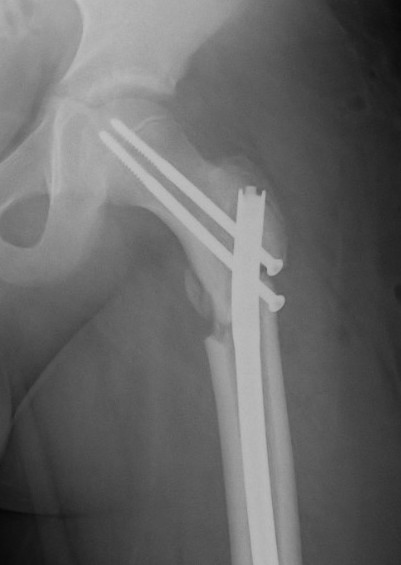

Subtrochanteric fracture

Subtrochanteric fracture likely causes by multiple drill holes / attempts

Cause

Too low screw entry

Multiple drill holes to get correct entry

Management

Intramedullary nail